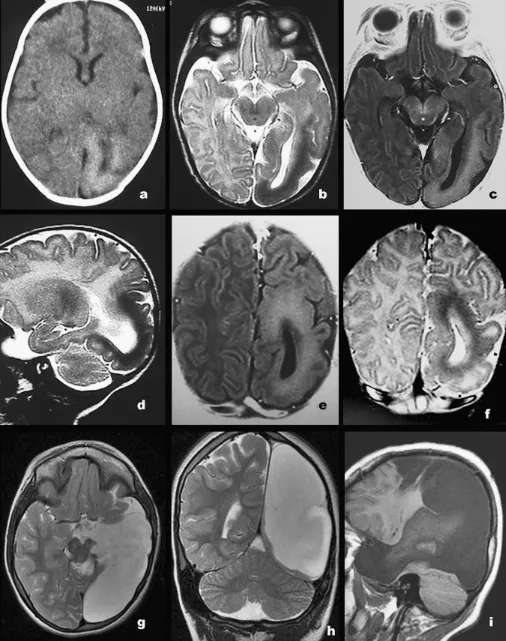

图2:病例4a轴位CT显示左侧颞叶、枕叶容积缩小,皮质显著增厚,以巨脑回为主;枕叶皮质光滑,脑沟回稀少,相对于未髓化的皮质下白质呈轻度高密度(CT)、T1高信号(b、e)、T2低信号(c、d、f);左侧侧脑室异常扩大。g-i术后MR(轴位T2、冠状T2、矢状T1)显示颞-顶-枕区脑脊液充填的手术残腔,病灶已完全切除。